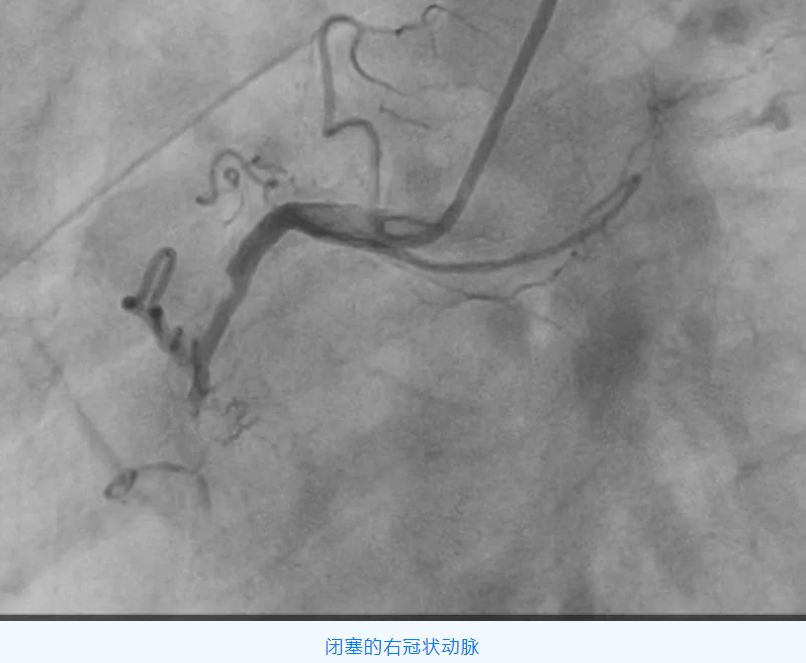

家住阎村的赵爷爷,今年75岁,近一年来反复出现胸痛、胸闷,行冠脉CTA检查发现冠状动脉三支病变,其中一根血管完全闭塞,需进一步行冠脉介入治疗。

冠状动脉慢性完全闭塞病变(CTO),即冠状动脉血管腔完全闭塞,且持续闭塞的时间大于 3 个月的病变。对于病人而言,成功开通 CTO 可以延长生命、改善心脏功能、增加心肌电活动稳定性,减少心律失常事件,而且还可以增加以后可能出现的冠状动脉闭塞事件耐受性及提高生活质量,越是年轻患者,开通 CTO 获益越大。

但该手术难度大、成功率低、并发症、再狭窄、再闭塞发生率高,被公认为是冠状动脉介入治疗的天花板。CTO 病变的开通成功率已成为评价医院心血管内科介入治疗水平高低的一个主要指标。